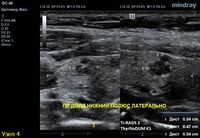

3) Узел правой доли, не прорастает капсулу щитовидной железы (0 баллов), больше широкий чем высокий (0 баллов), не имеет кальцинатов (0 баллов), с ровным четким контуром (0 баллов), изоэхогенный (1 балл), смешанной структуры (1 балл). Количество баллов 2, ACRTi-RADS2, ThyrNoDUMК1. Пункция не показана в связи с низким риском.